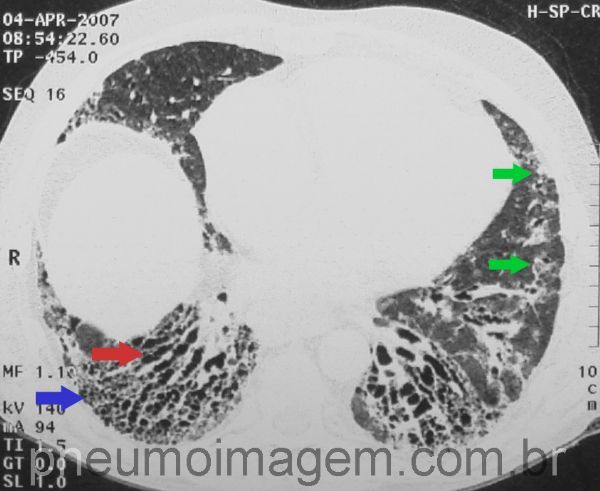

Opacidades em vidro fosco de predomínio periférico, nas regiões inferiores, com espessamento interlobular (setas verdes).

Faveolamento periférico-imagens em favo de mel (seta azul).

Bronquiectasias de tração (seta vermelha).

Dilatação do esôfago com nível hidraéreo (seta azul).

Chave: nível líquido.